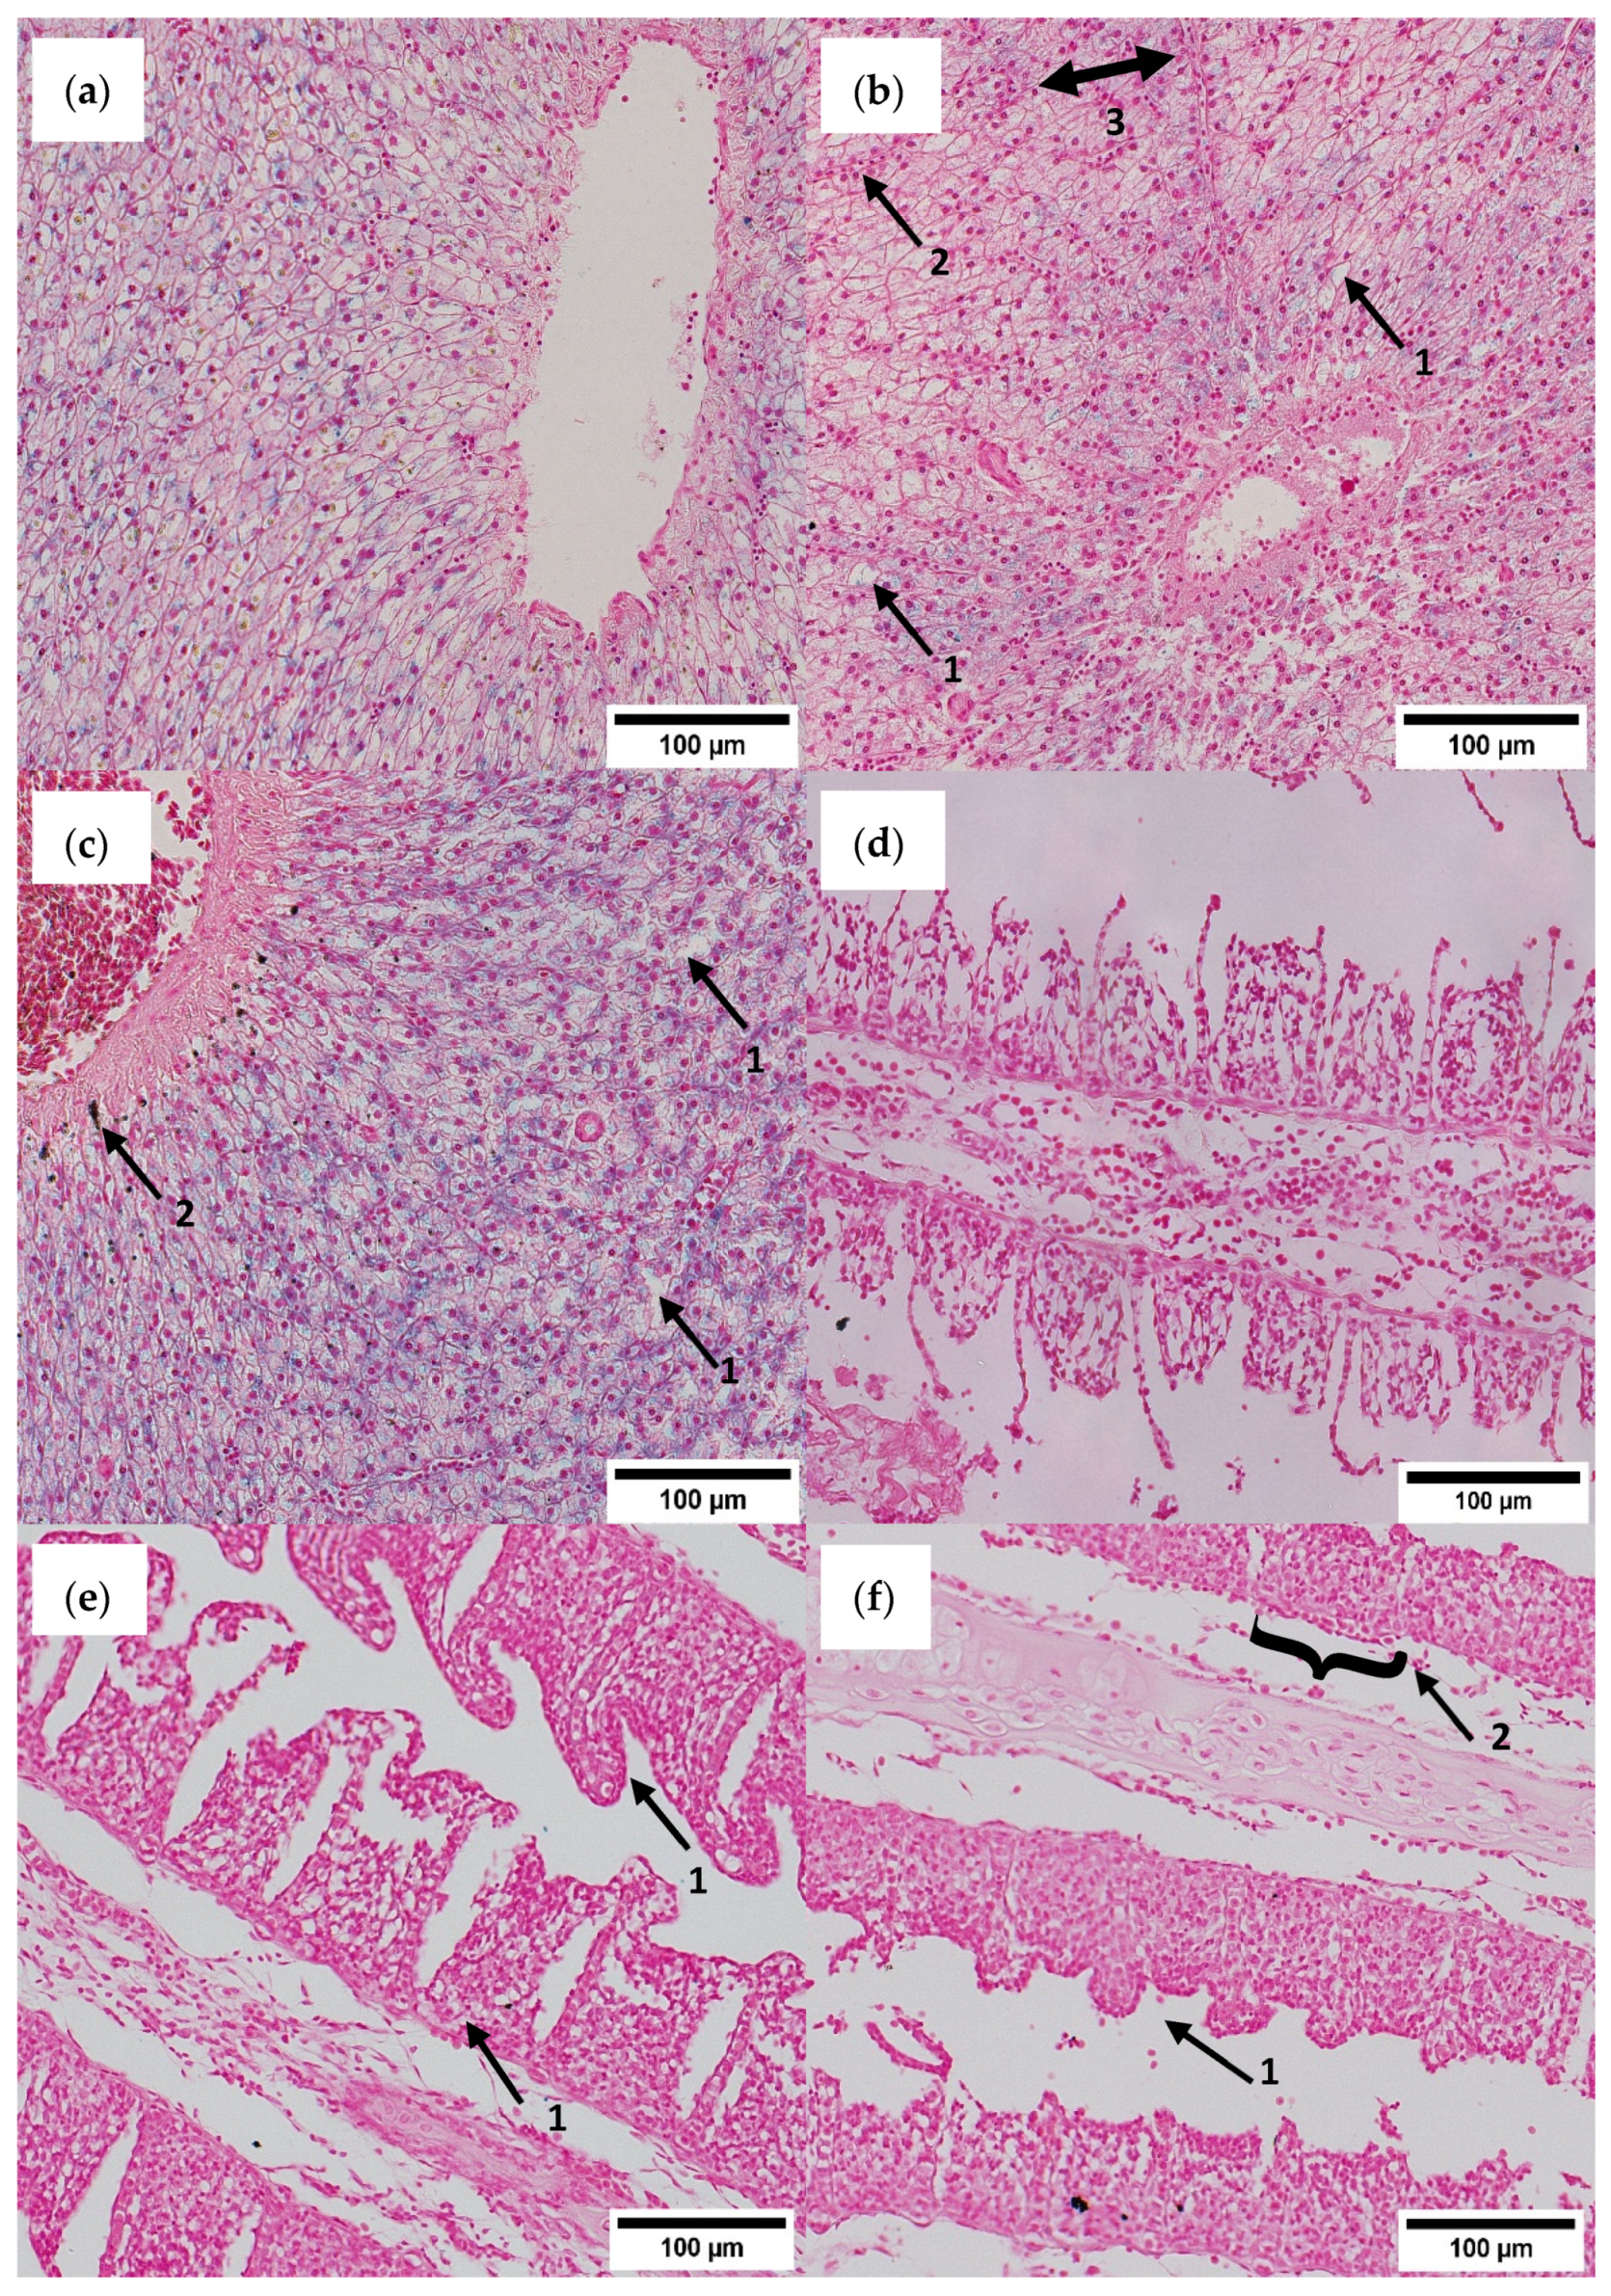

3.5. Histological Assessment

4.4. Histopathology and Gene Expression Profiling